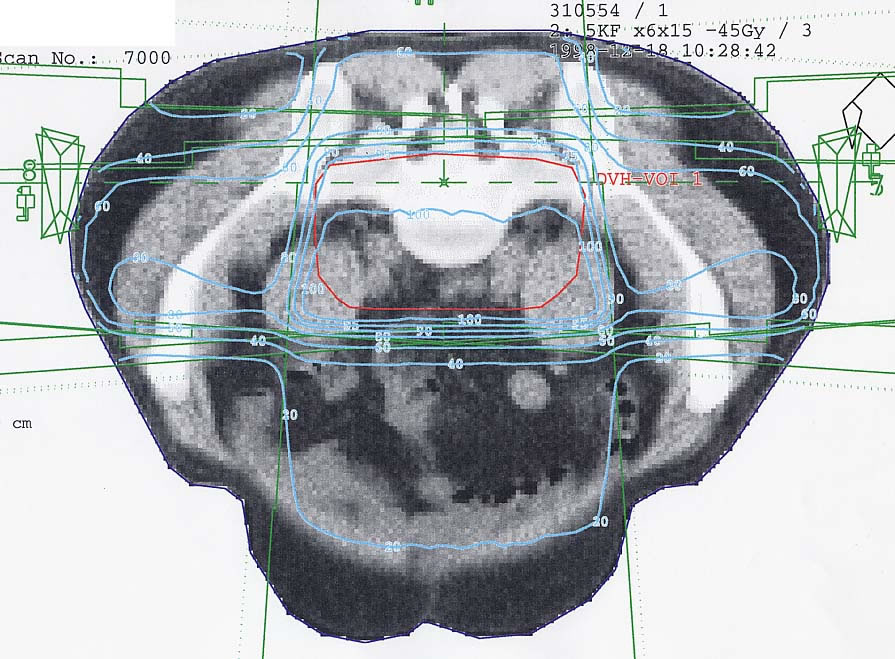

Rektumkarzinom (Enddarm): Bestrahlungsplan